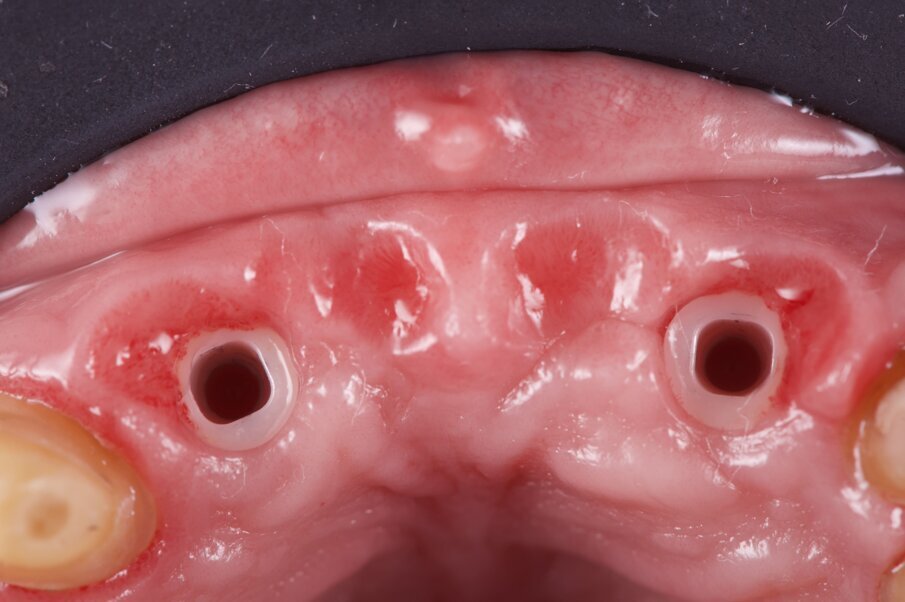

La rigenerazione ossea è stata ottenuta secondo l’impiego di biomateriale di origine bovina demineralizzato e stabilizzato con una membrana a lento riassorbimento in pericardio nativo fissata con dei chiodini in titanio (Fig. 23). Com’è noto la stabilità dell’innesto è un requisito indispensabile per ottenere una reale rigenerazione ossea stabile nel tempo. Dopo 4-6 mesi si effettua una radiografia di controllo eseguendo successivamente un opercolo perimplantare. In questo caso data la lieve deiscenza presente si è optato per l’impiego di un diatermocoagulatore per limitare il danno biologico ai tessuti limitrofi e mantenere inalterata la rivascolarizzazione della sede, inoltre non essendo un materiale metallico ma bensì ceramico, l’eventuale contatto viene disperso e non assorbito dall’impianto (Fig. 24). Data l’ottima stabilizzazione funzionale e volendo contenere i costi viene realizzata un’impronta digitale dell’arcata col primo provvisorio in situ e alla sua rimozione un’impronta dell’intera arcata con e senza gli scan body implantari (Fig. 25). Per mantenere l’opercolo ottenuto si utilizzano delle cappette di guarigione sempre in Zirconia che serviranno anche per stabilizzare i tessuti perimplantari (Fig. 26). In laboratorio, l’odontotecnico su nostra indicazione potrà elaborare i file ricevuti, valutando la possibilità di avvitare direttamente il manufatto, solo in caso di forte disparallelismo si opterà per la cementazione. Definita la procedura, verrà realizzato solo il provvisorio su impianti modificando il primo provvisorio che sarà riposizionato dopo il sezionamento dei quadranti (Figg. 27, 28). Dopo il posizionamento del nuovo provvisorio rileviamo una nuova impronta studio (Fig. 29) che analizziamo col software dedicato dello scanner digitale utilizzato.

Fig. 25_Dopo opercolarizzazione si provvede a rilevare l’impronta con appositi transfer che per le impronte digitali si chiamano scan body e si differenziano per il tipo di impianto e per il tipo di scanner intraorale utilizzato.

Fig. 26_Al termine dell’impronta si posizionano delle cappette di guarigione in zirconia in grado di stabilizzare il tessuto gengivale.

Fig. 30_Dopo un breve periodo di condizionamento è possibile valutare le fovee mucose ovattate e il supporto pericoronale.